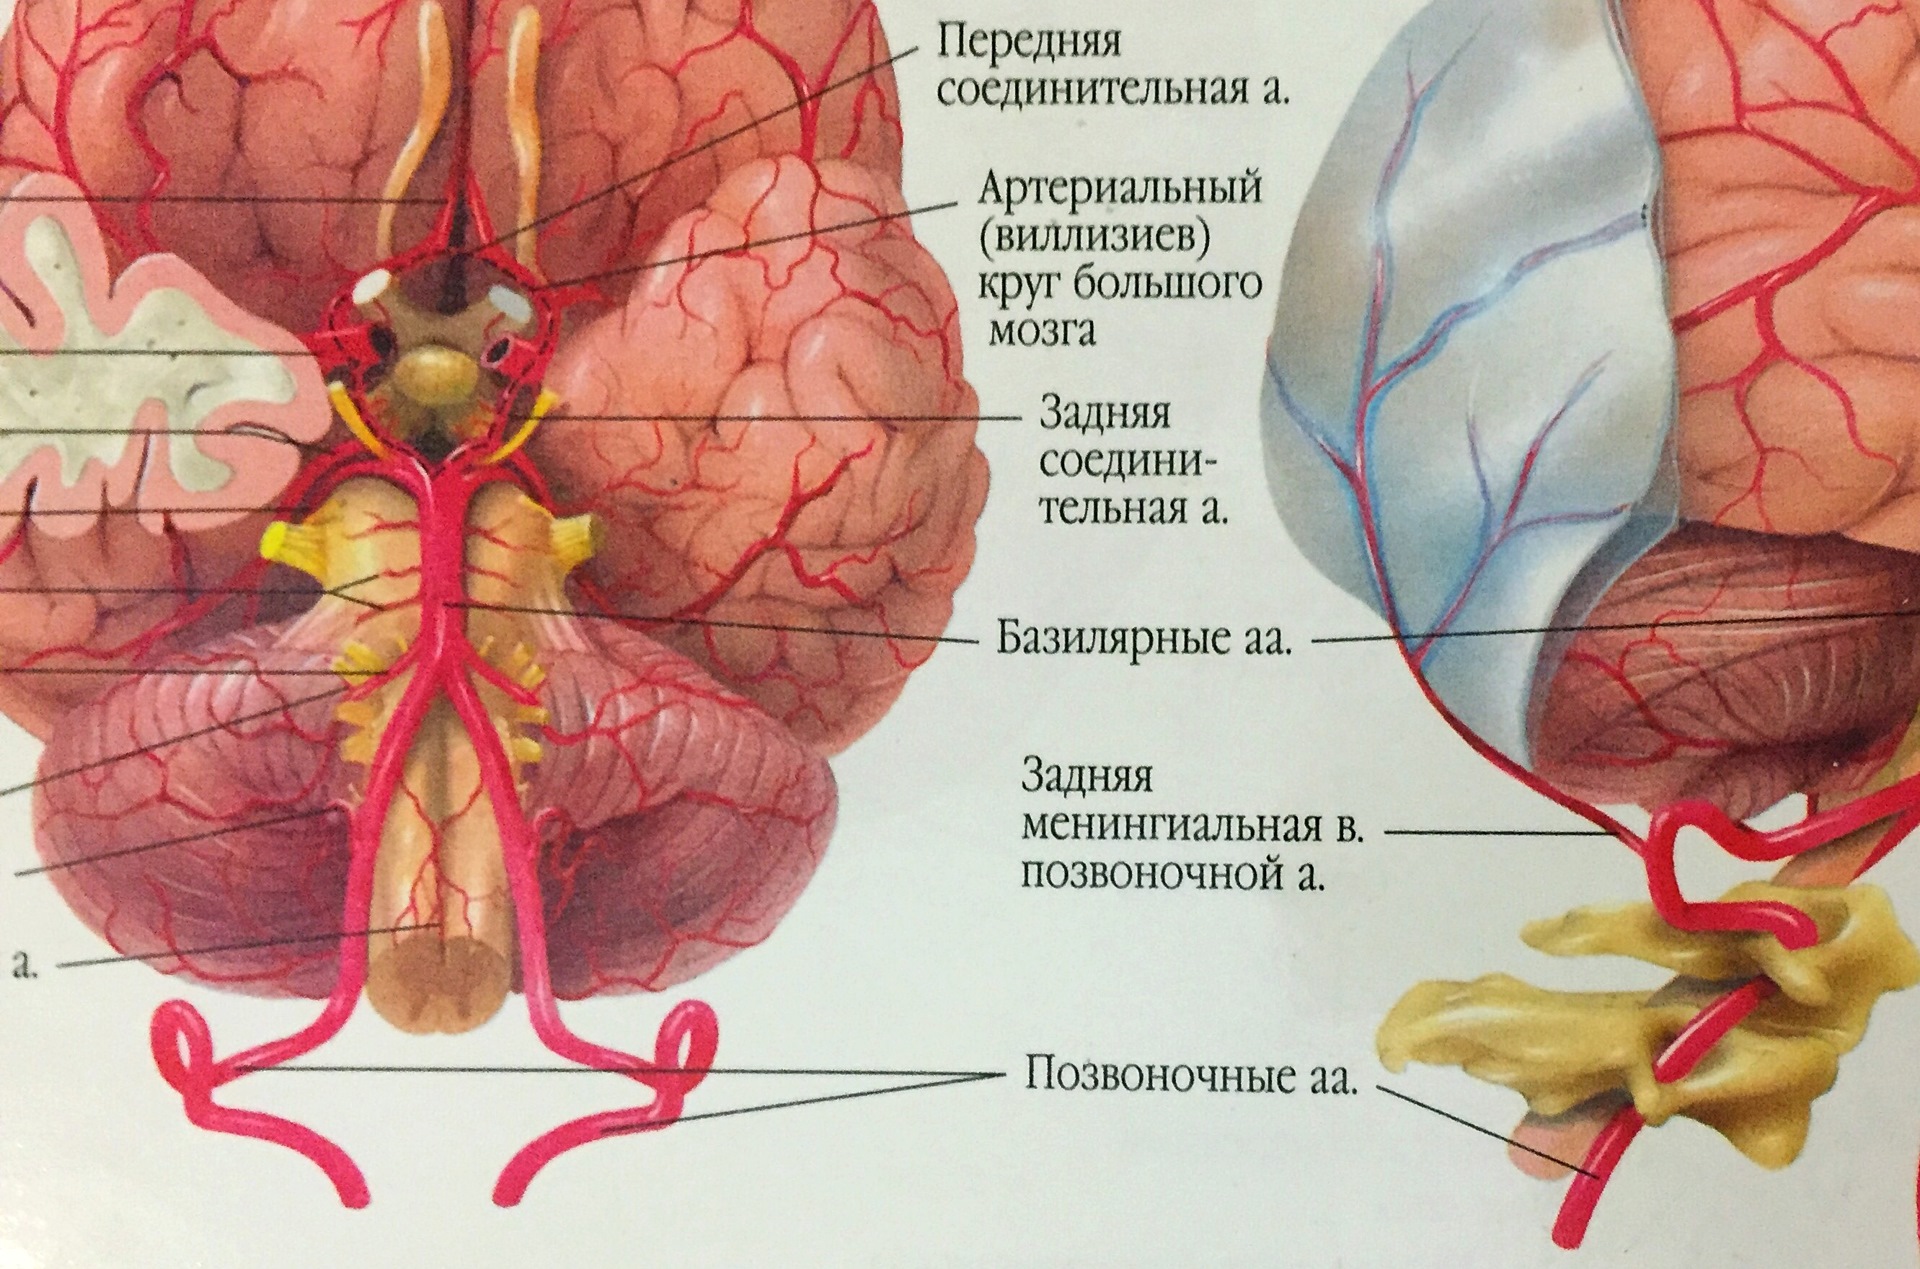

Анатомия: Задняя соединительная артерия мозга